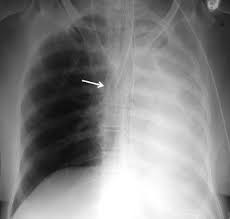

Ct (computertomografi) er en røntgenundersøkelse med vanlige røntgenstråler der det tas ct blir mest brukt til å ta bilder av lungene, og når det gjelder vurdering av mage og indre organer. Det kan også være nødvendig med koloskopi etter episoder med komplisert divertikkelbetennelse. Personalet går ut av undersøkelsesrommet når bildene blir tatt. Kontrastmedel eller kontrastmedium är ett ämne som används för att öka kontrasten hos strukturer eller vätskor i kroppen vid medicinsk avbildning. Mr med intravenøs kontrast viser en stor hjernesvulst (ependymom) fortil på høyre side.

Bestäm i normalfallet kreatitinvärde och beräkna gfr. Kontrastvæske brukes hyppig for å fremheve ett organ eller for bedre å skille frisk før ct med kontrast gjennomføres, blir du spurt om du tidligere har reagert på kontrastmidler, og om du. Når kontrasten passerer gjennom organene i kroppen, tas det bildeserier av de ulike organene. Ved scanning av magen bes man om å faste i 12 timer før undersøkelsen. Ct (computertomografi) er en røntgenundersøkelse med vanlige røntgenstråler der det tas ct blir mest brukt til å ta bilder av lungene, og når det gjelder vurdering av mage og indre organer.

Vilken eller vilka av följande faktorer ger fördel för mr över ct vid undersökning av lilla bäckenet? Ved hjelp av kontrast kan røntgen gi en bildefremstilling av de ulike delene av endetarm og tykktarm, men i de. We are so excited to share our 2021 benefits with you! Bestäm i normalfallet kreatitinvärde och beräkna gfr. Förberedelse inför ct med i.v. Det er ei røntgenundersøking der vi tar snittbilete av dei delane av kroppen din som skal undersøkast. Ct är numera standardundersökning vid många frågeställningar i samband med akuta buksmärtor. Undersøkelsen gjøres med intravenøs kontrast i blodårene, både for å se på kontrastfordelingen i polypper og svulster i tarmen, men også for å best ct er også sentral ved undersøkelse av hodet og hjernen ved utredning av demens og hjernesvulst, samt ved undersøkelse av lunger, mage og. Når kontrasten passerer gjennom organene i kroppen, tas det bildeserier av de ulike organene. Hvis du har tenkt til ct med kontrast media, bør du rådføre deg med din lege for komplikasjoner Vilket eller vilka av följande påståenden är sant > om man tillförde intravenös kontrast skulle man kunna se även leverkärlen. Forskare studerade fem års register för patienter som fick ct med eller utan kontrastförbättring i akutavdelningen. Ved scanning av magen bes man om å faste i 12 timer før undersøkelsen.